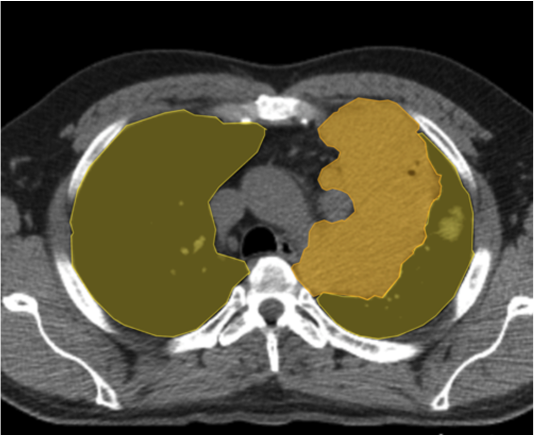

- CNNs (Convolutional Neural Networks) and U-Net are widely adopted for identifying structures, segmenting organs, and detecting anomalies with minimal error.

- High-quality annotated data fuels accurate AI models, allowing researchers to train algorithms effectively for multiple imaging modalities like MRI, CT, and PET.

- Advanced AI converts 2D scans into detailed 3D models, assisting surgeons in pre-operative planning and precision medicine.

Australian research teams are using AI for improved cardiac imaging, predicting risks, and assisting in surgical planning.